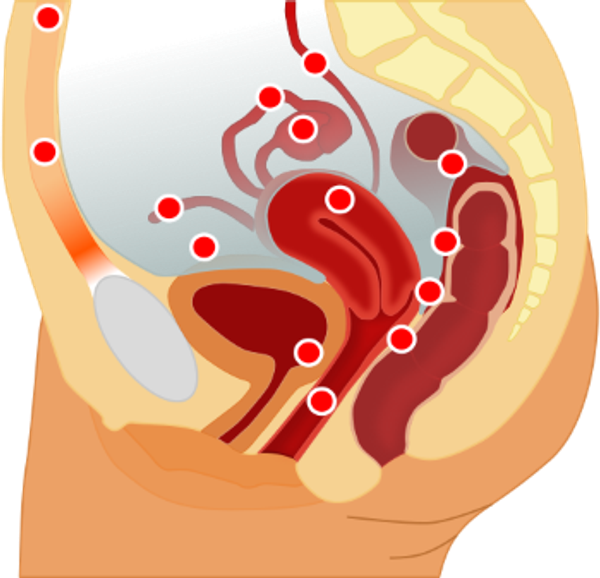

Leestijd: 5 minutenEndometriose ist eine chronische Erkrankung, die nur bei Frauen auftritt. Zellen der Gebärmutterschleimhaut (Endometrium), die normalerweise das Innere der Gebärmutter auskleiden, treten in diesem Fall auch an deren Außenwand auf. Dies betrifft in der Regel die Bauchhöhle, das Bauchfell und die Organe im Beckenbereich. Frauen, die an Endometriose leiden, haben oft starke Menstruationsbeschwerden, Schmerzen beim Wasserlassen und beim Stuhlgang (oft während der Menstruation), Schmerzen und/oder Blutverlust während und nach dem Geschlechtsverkehr sowie Müdigkeit.

Die Endometriose entsteht aller Wahrscheinlichkeit nach dadurch, dass während der Menstruation Blut durch die Eileiter in die Bauchhöhle gelangt. Dieses Blut enthält Zellen, die sich in der Bauchhöhle einnisten können, wo sie dann zu wachsen beginnen. Diese Einnistung kann oberflächlich erfolgen, zum Beispiel im Bauchfell, aber auch tief im Darm, in den Eierstöcken oder in der Blase. Hier durchlaufen diese Zellen, genau wie die Zellen der Gebärmutterschleimhaut, unter dem Einfluss des Hormons Östrogen den gleichen Zyklus. Während dieses Zyklus verdicken sie sich und bluten während der Menstruation.